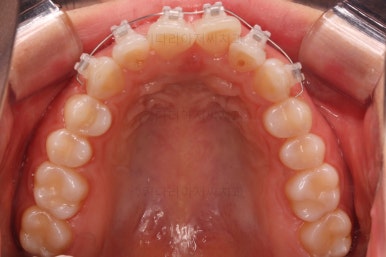

벌써 치료 종료시의 모습입니다.

치료는 총 5개월이 걸렸네요.

일반적으로 부분교정은 6개월 전후로 치료기간이 걸리긴 하고 이번 환자분의 경우는 삐뚤어진 정도가 심한 편이 아니라서 짧게 걸린 편이었어요.

치료결과는 매우 만족하셨습니다.

삐뚤었던, V자로 꺾여있던 나비앞니치아가 가지런해졌어요.

양치질도 훨씬 편해져서 장기적으로 구강건강에도 도웅미 되실 거에요.

다시 틀어지지 말라고 앞니 안쪽에 유지장치를 부착해 주고 마무리를 했습니다.